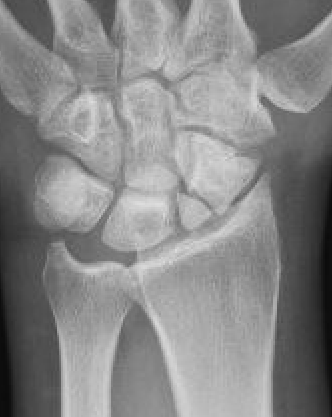

Definition

Scaphoid non union advanced collapse

Nonunion with resultant radiocarpal and midcarpal OA

Pathology

Scaphoid nonunion

- flexion deformity and abnormal joint mechanics

- radiocarpal osteoarthritis

- progresses from radial styloid / scaphoid fossa / midcarpal joint

- radiolunate joint preserved